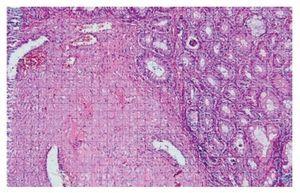

¿ Figura 1. Imagen microscópica del endometrioma.